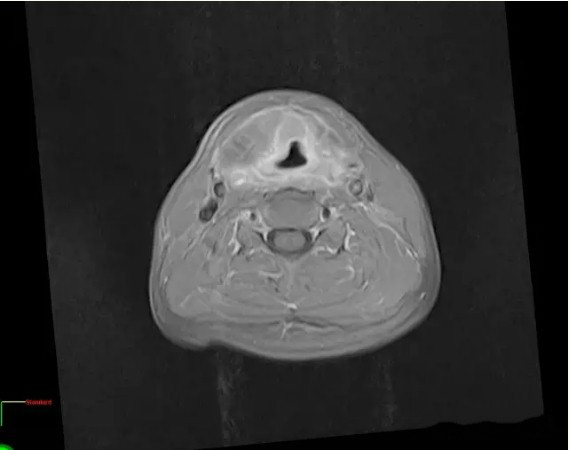

淄博质子中心-喉癌质子治疗 十五个月复查 肿瘤消失时间:2024-08-19

喉癌质子治疗病例:患者,男,60岁 现病史:患者5年前无明显诱因出现声音嘶哑,无咳嗽、咳痰、咳血,无进食梗阻感、发热,患者未予特殊处理。2月前声音嘶哑症状较前加重,于2009年11月13就诊于南方某医院,入院行“电子耳鼻喉内镜检查”示:会厌结节处新生物。排除手术禁忌症后于2009年11月18于全麻下行“激光喉镜显微镜下喉新生物活检术”,活检病理示:左喉室新生物、右声带新生物、会厌结节新生物:鳞状细胞癌Ⅱ级;右侧室带新生物:鳞状上皮增生。2009年11月23就诊于该院门诊行喉部强化CT示:左侧口咽、喉咽壁增厚,双侧声带、前联合、杓会厌皱襞明显增厚伴囊实样肿块,周围间隙欠清,包裹气管受压;该院建议患者行手术治疗,患者及家属拒绝,现为求进一步治疗,特来我院就诊,经各科专家会诊,行质子治疗。

随访15个月,未见复发征象!